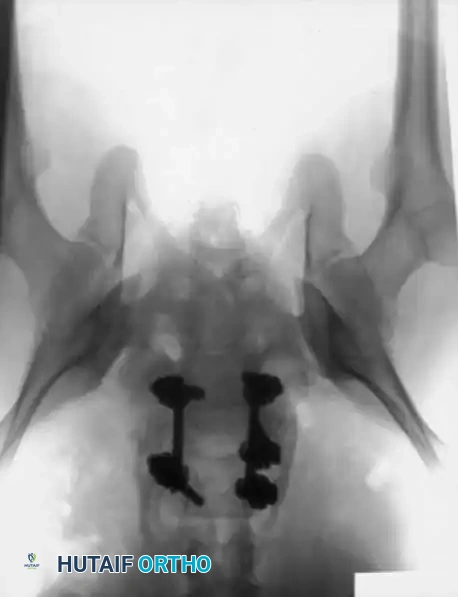

Comprehensive preoperative planning requires full-length standing scoliosis films to calculate pelvic parameters (Pelvic Incidence, Pelvic Tilt, Sacral Slope).

The patient is positioned prone on a radiolucent Jackson spinal table. The abdomen must hang completely free to decrease intra-abdominal pressure, thereby reducing epidural venous engorgement and intraoperative bleeding. Hips are extended to maximize lumbar lordosis during the fusion phase.

Surgical Pitfall: In severe dysplastic slips, the anatomy is grossly distorted. The L5 lamina

Associated Surgical & Radiographic Imaging